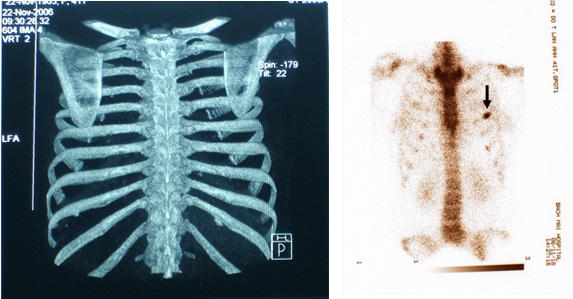

BN được chỉ định làm xạ hình xương toàn thân để kiểm tra tổng thể toàn bộ hệ thống xương, phát hiện ổ di căn xương sườn số 4 trái.

Bệnh nhân được tiếp tục điều trị phác đồ FOLFIRI 6 chu kỳ, thuốc chống huỷ xương. Hiện tại, khám lại BN sức khoẻ tốt, bệnh ổn định và trở về công việc hàng ngày bình thường.

Bàn luận: Trong điều trị ung thư việc xác định đúng giai đoạn bệnh có ý nghĩa quyết định phương pháp điều trị, từ đó mang lại hiệu quả điều trị tốt nhất cho người bệnh. Nếu chỉ dùng các phương pháp chẩn đoán thông thường rất dễ bỏ sót tổn thương qua đó đánh giá không đúng giai đoạn bệnh. Sự ra đời của các máy SPECT, PET, SPECT/CT, PET/CT ghi hình ở mức độ tế bào, mức độ phân tử, theo nguyên tắc chuyển hoá khi chưa có sự thay đổi về giải phẫu thực sự, là bước tiến quan trọng trong việc phân loại đúng, sớm giai đoạn bệnh cũng như việc điều trị ung thư. ở BN này, bằng các kỹ thuật chẩn đoán thông thường (ngay cả với CT 64 dãy đầu dò) đều cho kết quả hoàn toàn bình thường, nhưng khi dùng kỹ thuật xạ hình bằng máy SPECT đã phát hiện ổ di căn xương trên xạ hình xương thì thái độ điều trị đã hoàn toàn thay đổi. BN được tiếp tục điều trị hoá chất và chống huỷ xương, hiện tại bệnh nhân khoẻ mạnh, bệnh ổn định.